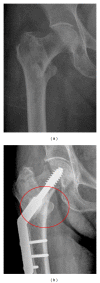

Introduction: Intertrochanteric hip fractures occur in the proximal femur. They are very common in the elderly and are responsible for high rates of morbidity and mortality. The authors hypothesized that adding an autologous bone marrow stem cells concentrate (ABMC) to a hydroxyapatite scaffold and placing it in the fracture site would improve the outcome after surgical fixation of intertrochanteric hip fractures.

Material and methods: 30 patients were randomly selected and divided into 2 groups of 15 patients, to receive either the scaffold enriched with the ABMC (Group A) during the surgical procedure, or fracture fixation alone (Group B).